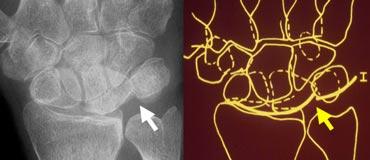

Ca lâm sàng 2

Phân tích:

1. Mất tính song song tại khớp TL (tháp-nguyệt) do xương tháp và xương nguyệt chồng lên nhau.

2. Xương móc và xương nguyệt cũng chồng lên nhau.

3. Có sự song song giữa xương quay, xương nguyệt, cực gần xương thuyền và cực gần xương đầu. Như vậy, các xương này tạo thành một khối thống nhất.

4. Cũng có sự song song giữa xương tháp, xương móc, cực xa xương đầu, xương thang và cực xa xương thuyền.

5. Gãy xương đầu và xương thuyền.

Các dấu hiệu này cho thấy đây là trật khớp quanh nguyệt kèm gãy xương thuyền và xương đầu (transscaphoid, transcapitate perilunate fracture-dislocation).

Bên trái là cùng một ca lâm sàng với đường kẻ chỉ ra đường gãy-trật khớp.

Cùng ca lâm sàng với tư thế chếch và tư thế nghiêng bổ sung, cho thấy tình trạng trật khớp ra phía sau (dorsal dislocation).